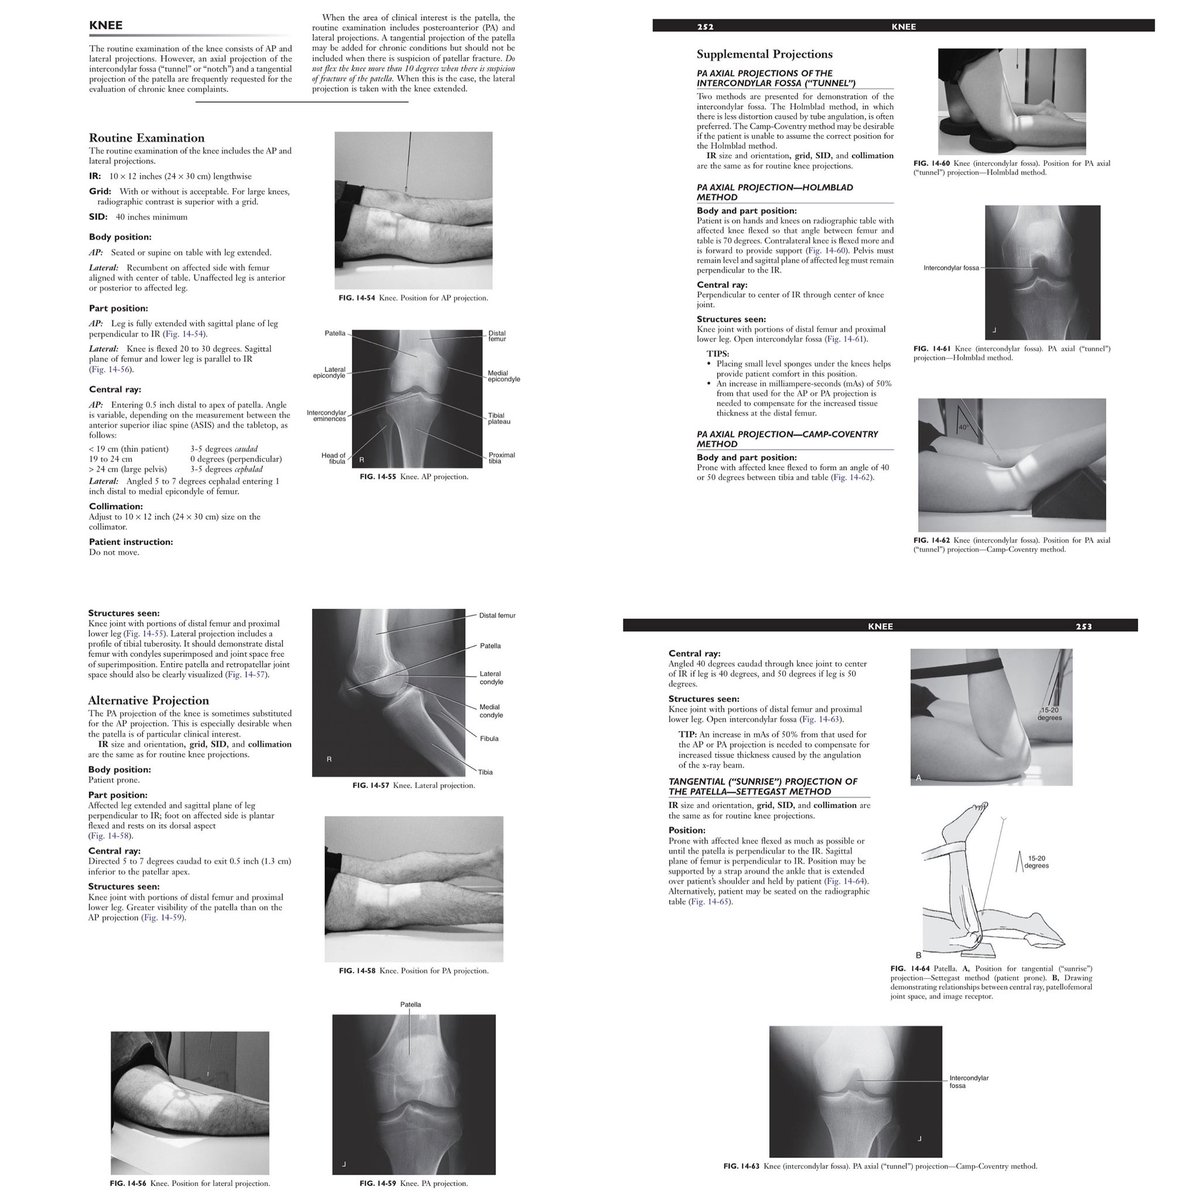

#radiology #radiography #xray #radiographer #radtech #srtle

من الاسئلة الاكثر أهمية في تصوير الركبة بالأشعة السينية فلنتشارك في الحل

SELF-TEST:

POSITIONING OF THE LOWER LIMB

Answer the following questions by selecting the best choice.

Reference (Merrill’s Atlas 12 edition)